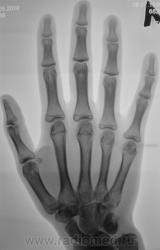

Пациентка направлена хирургом в рентгеновский кабинет для рентгенографии кисти и лучезапястного сустава. Вроде-бы, была и травма, после которой появилась боль в лучезапястном суставе.

перелом крючковидной кости, м.б и гороховидной (по поводу последней не очень уверен)

Укладки на трехгранную кость, она смещена каудально и радиально, структура неоднородная, но на счет перелома не уверена, а вот вывих трёхгранной кости есть.

Смущает перестройка структуры костной ткани, помечено стрелками.

Похоже на кисты (здесь - врождённые)

А может ГКО?